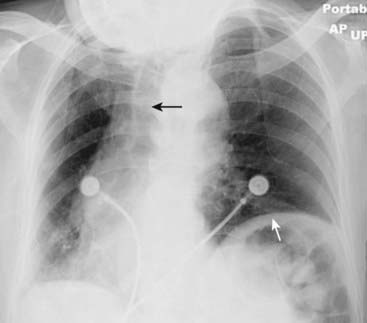

image

Figure 2-10 Underpenetrated frontal chest radiograph.

The spine (solid black arrow) is not visible through the cardiac shadow. The left hemidiaphragm is also not visible (dotted black arrows) and the degree of underpenetration makes it impossible to differentiate between actual disease at the left base versus nonvisualization of the left hemidiaphragm from underpenetration. A lateral radiograph of the chest would help to differentiate between artifact of technique and true disease.